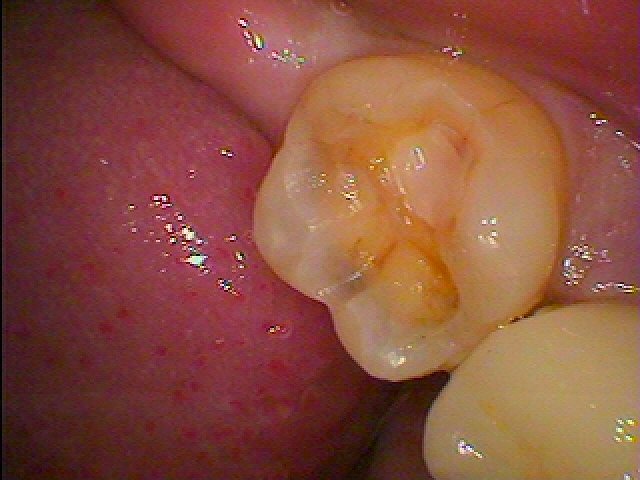

右下7番、銀歯の下が黒く虫歯の可能性があります

外してみると虫歯になっていました